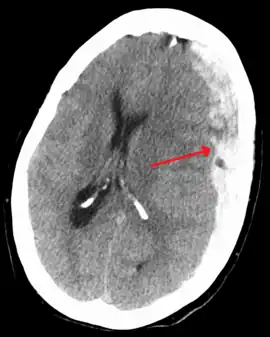

Subdural hematoma as marked by the arrow with significant midline shift

On a CT scan, subdural hematomas are classically crescent-shaped, with a concave surface away from the skull. However, they can have a convex appearance, especially in the early stages of bleeding. This may cause difficulty in distinguishing between subdural and epidural hemorrhages. A more reliable indicator of subdural hemorrhage is its involvement of a larger portion of the cerebral hemisphere. Subdural blood can also be seen as a layering density along the tentorium cerebelli. This can be a chronic, stable process, since the feeding system is low-pressure. In such cases, subtle signs of bleeding—such as effacement of sulci or medial displacement of the junction between gray matter and white matter—may be apparent.